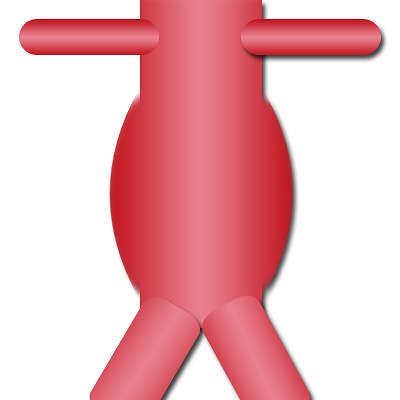

Le diamètre normal de l’aorte se situe entre 20 et 25 mm. Au dessus on parle d’anévrysme, c’est-à-dire une dilatation anormale d’un vaisseau. En général, on opère ces anévrysmes lorsqu’ils ont atteint 50 mm de diamètre (avant, une surveillance de leur taille est indispensable au moins de manière annuelle).

Anévrysme de l’aorte abdominale

L’évolution d’un anévrysme en fait sa gravité. Il grossit inexorablement et risque de se rompre (pouvant entraîner le décès par hémorragie interne). Il peut aussi être à l’origine d’embolie (un caillot sanguin) dans les artères sous-jacentes (iliaques, fémorales…) et être alors responsable d’une ischémie aiguë de membre avec un risque d’amputation. Plus rarement, il peut comprimer les organes de voisinage, notamment l’uretère, et être responsable d’une dilatation des voies urinaires.